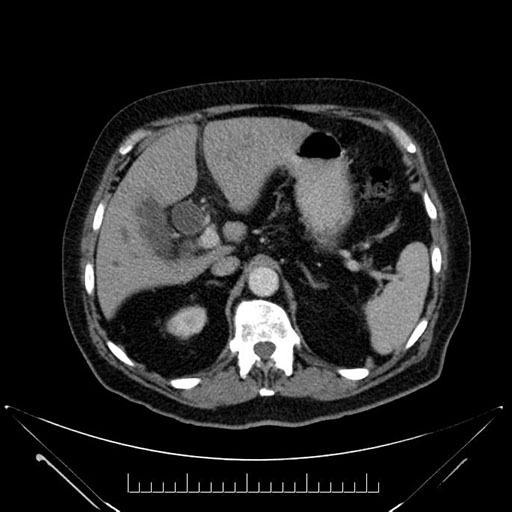

Axial - 3 months prior